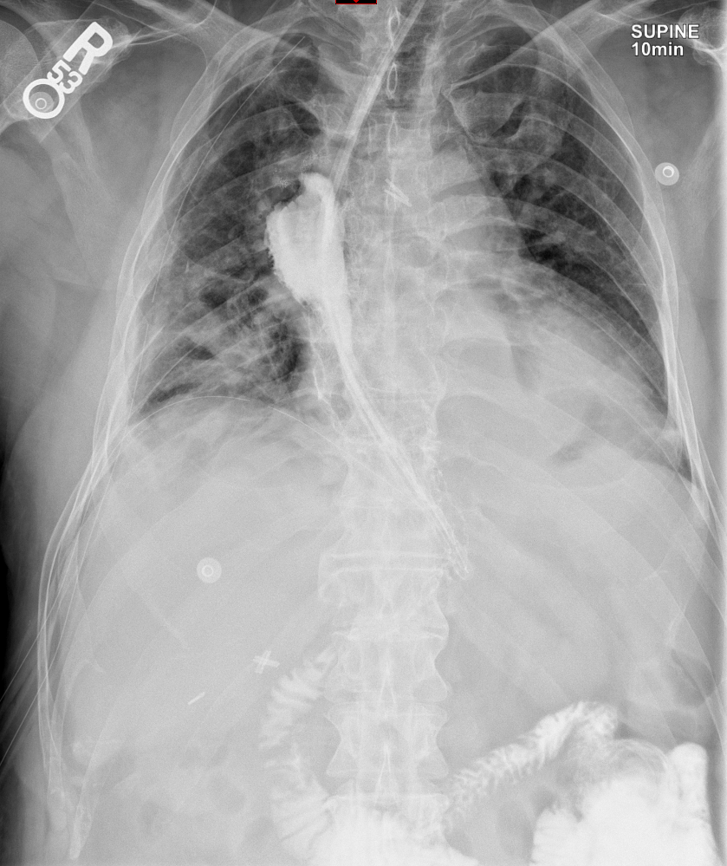

- The technologist will obtain a scout radiograph(s) to include the chest and upper abdomen to determine the location of the surgical chain sutures or surgical staples

(key image 1).

- The esophagogastric anastomosis is usually located at the level of the aortic arch or just below it.

- The technologist will then obtain a post-procedure overhead of the chest.

(key image 7).